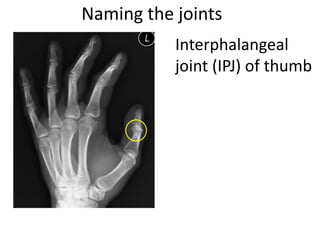

This document provides an overview of hand anatomy including:

- Naming the bones, joints, tendons, nerves and skin landmarks of the hand and wrist.